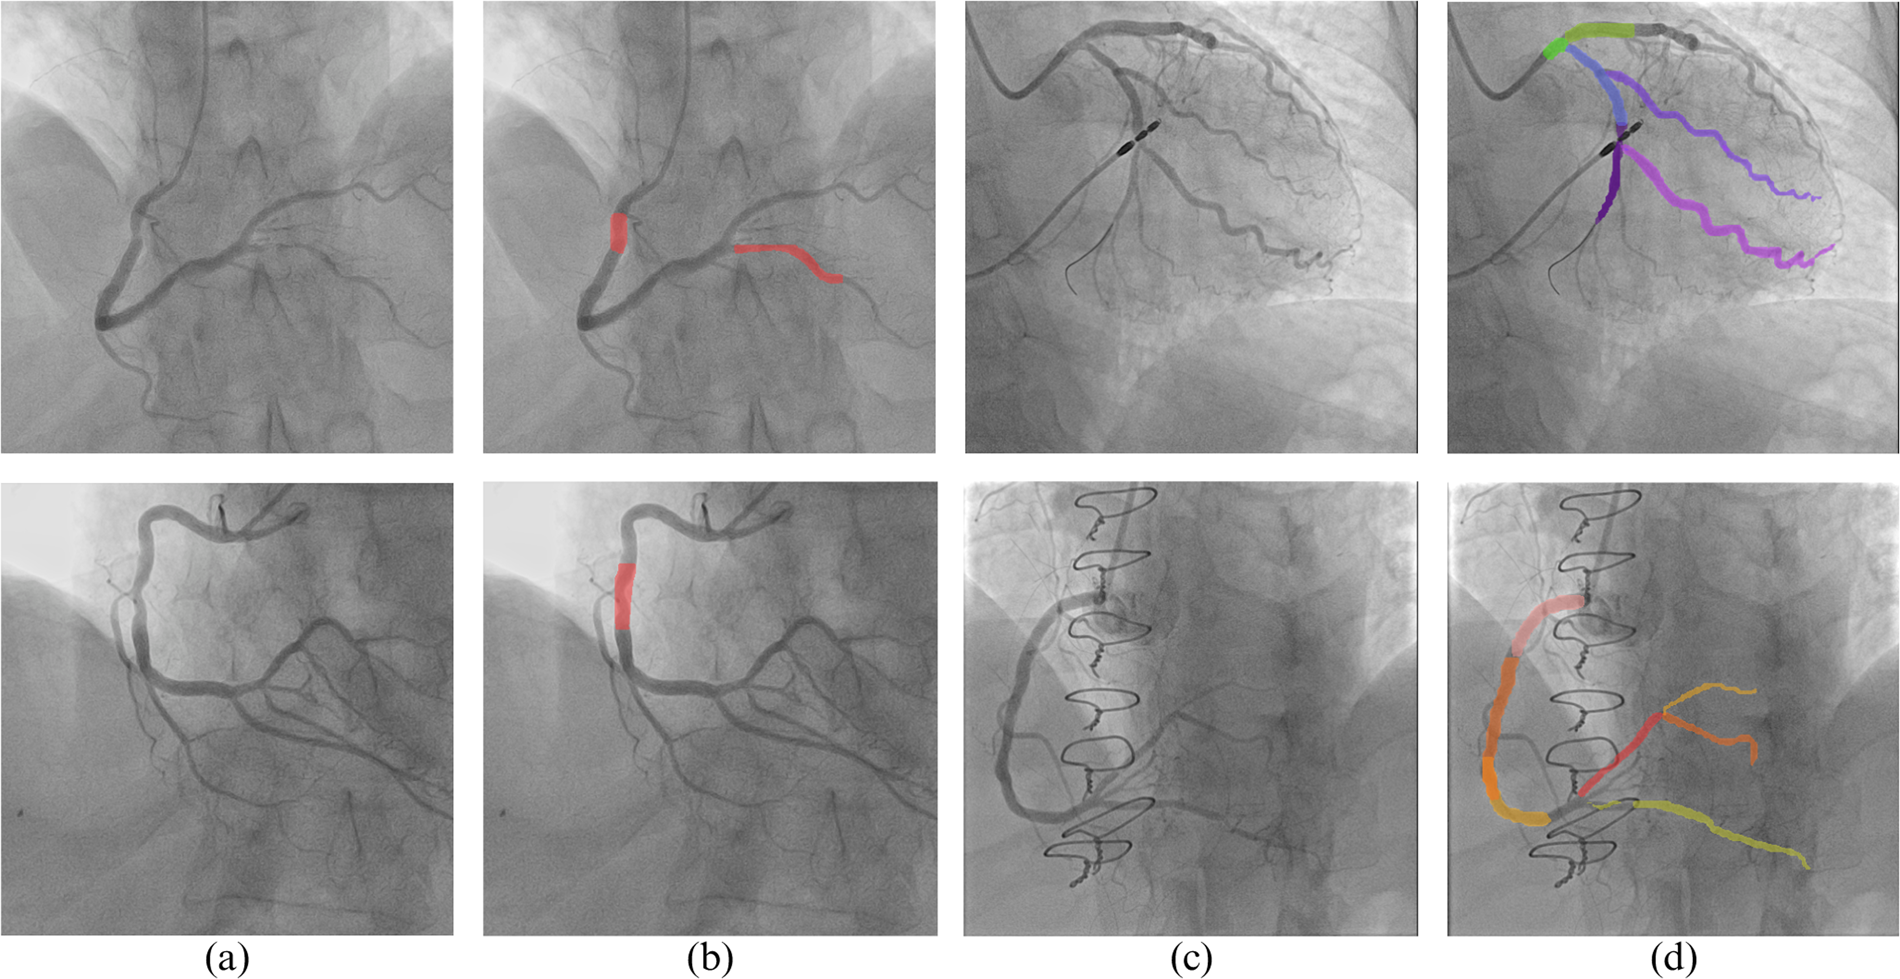

Fig. 5

YOLOv8 results on out-of-distribution images: (a) and (c) original images; (b) stenosis detection result using the proposed method; (d) coronary region classification results using the proposed method.